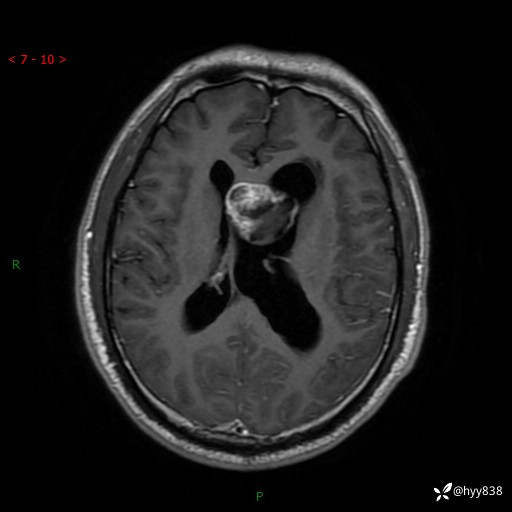

颅脑MRI平扫+增强